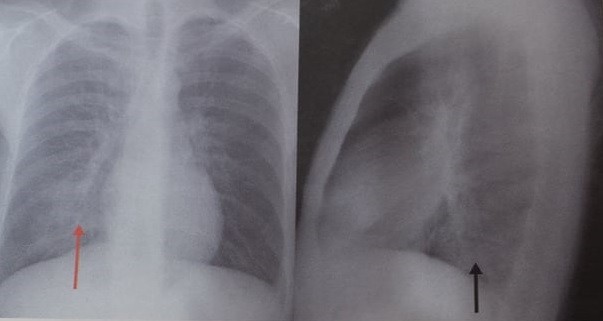

Afectiunea cunoscuta sub numele de fibroza pulmonara se caracterizeaza prin prezenta unor cicatrice in tesutul pulmonar. Specialiştii apreciează însă că numărul bolnavilor nediagnosticaţi ajunge la 1000 de persoane. Fibroza pulmonara poate fi un efect secundar al unei alte afectiuni. Un prim pas este suspectarea unei boli pulmonare fibrozante de la prima prezentare a pacientului la medic medic de familie internist cardiolog pneumolog etc.

La unii oameni boala ramane aceeasi timp de multi ani. Factori de risc. Netratată boala este la fel de agresivă precum cancerul pulmonar jumătate din pacienţi mor în primii 3 ani de la diagnostic. Fibroza pulmonară este o afecțiune cunoscută și sub denumirea de pneumopatie interstițială difuză fibrozantă caracterizată prin înlocuirea patologică a interstițiului pulmonar cu un țesut conjunctiv sclerozant secundar depunerii la nivel interstițial și alveolar a unor componente celulare inflamatorii fibroza pulmonară este o afecțiune mutilantă care determină în.